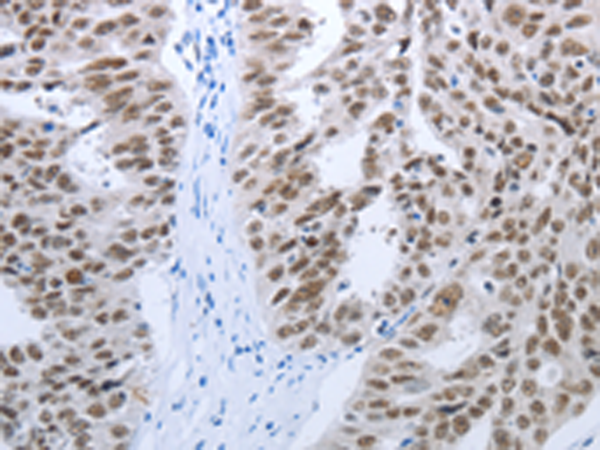

分类: 科研抗体货号: P11103别名: 123F2; RDA32; NORE2A; RASSF1A; REH3P21应用: WB,IHC反应种属: Human, Mouse